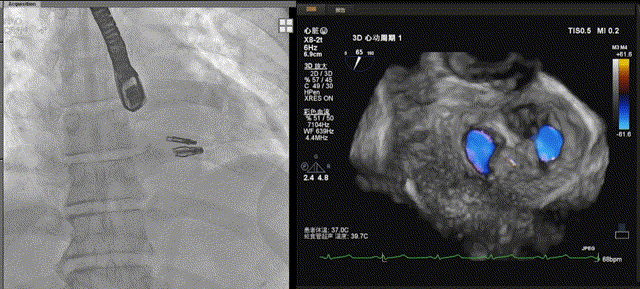

患者全麻后,在经食道超声心动图和X射线引导下,经股静脉入路,将申淇淇麟®系统瓣膜夹(长宽型号)顺利送至二尖瓣A2/P2区域,经调整位置使瓣膜夹垂直对合缘,跨瓣,应用单瓣叶独立捕获功能,成功地分别捕捉二尖瓣前叶和后叶,经超声心动图反复确认瓣叶夹持牢固,反流量减少,遂释放瓣膜夹。

TEE显示,二尖瓣夹植入后反流减少

但由于后叶脱垂宽度较大,第一枚夹子释放后活动度较大,为稳定第一枚瓣膜夹并进一步减少反流,遂决定植入第二枚瓣膜夹(长窄型号),第二枚瓣膜夹释放后,经超声心动图评估,两枚瓣膜夹均位置和功能良好,瓣膜夹活动度低,反流进一步减少,平均跨瓣压差为4mmHg,手术顺利完成。